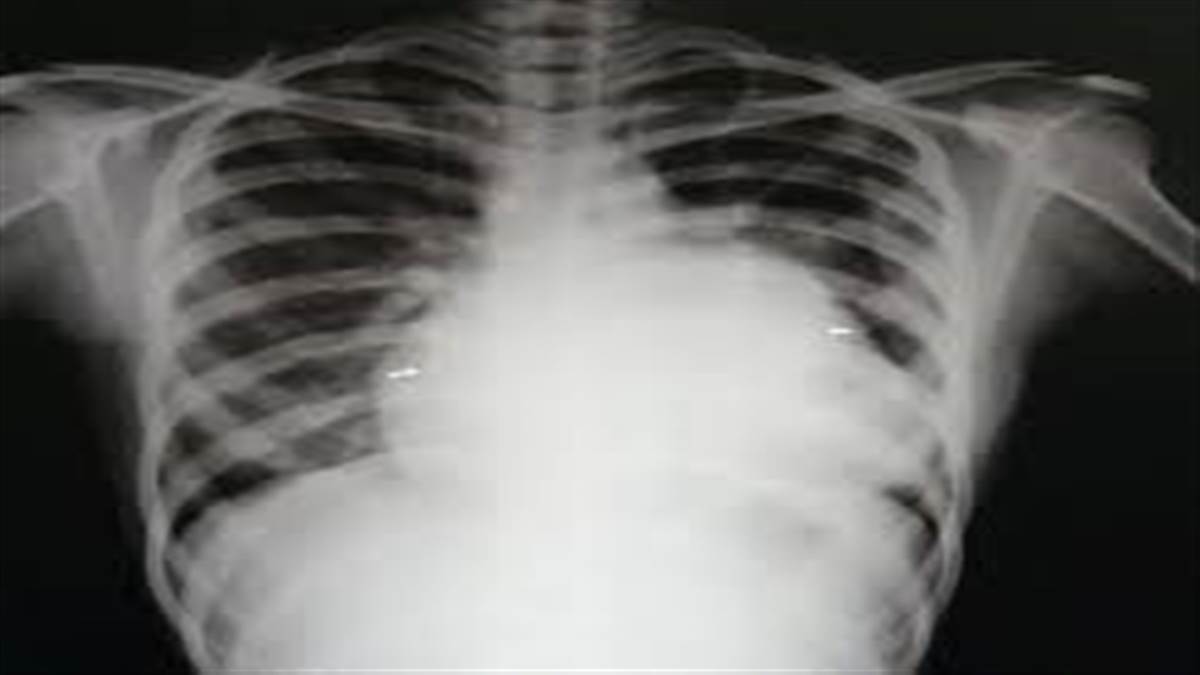

ਦਰਅਸਲ ਮੈਡੀਕਲ ਕਾਲਜ ਸਥਿਤ ਕਾਰਡਿਕ ਵਿਭਾਗ ਦੇ ਪ੍ਰੋਫੈਸਰ ਡਾ. ਪਰਮਿੰਦਰ ਸਿੰਘ ਮੰਗੇੜਾ ਤੇ ਉਨ੍ਹਾਂ ਦੀ ਟੀਮ ਨੇ ਤਿੰਨ ਘੰਟੇ ਦੀ ਸਰਜਰੀ ਦੇ ਬਾਅਦ ਔਰਤ ਦੀ ਜਾਨ ਬਚਾਈ ਹੈ। ਡਾ. ਮੰਗੇੜਾ ਅਨੁਸਾਰ ਲਿਊਟੇਂਬੇਚਰ ਸਿੰਡ੍ਰੋਮ ਦੀ ਸ਼ਿਕਾਰ ਕਰੋੜਾਂ ਔਰਤਾਂ ਵਿਚੋਂ ਕੋਈ ਇਕ ਹੁੰਦੀ ਹੈ। ਬਲਵਿੰਦਰ ਕੌਰ ਨਾਮ ਦੀ ਇਹ ਔਰਤ ਜਦੋਂ ਮੈਡੀਕਲ ਕਾਲਜ ਨਾਲ ਸਬੰਧਤ ਗੁਰੂ ਨਾਨਕ ਦੇਵ ਹਸਪਤਾਲ ਵਿਚ ਆਈ ਸੀ ਤਾਂ ਉਸ ਨੂੰ ਸਾਹ ਲੈਣ ਵਿਚ ਤਕਲੀਫ ਸੀ ਤੇ ਨਿਮੋਨੀਆਂ ਤੋਂ ਪੀੜਤ ਸਨ। ਧੜਕਨ ਤੇਜ਼ ਹੋ ਰਹੀ ਸੀ। ਮੈਡੀਸਨ ਵਿਭਾਗ ਦੇ ਡਾਕਟਰਾਂ ਨੇ ਇਲਾਜ ਸ਼ੁਰੂ ਕੀਤਾ ਪਰ ਮਰਜ ਸਮਝ ਨਹੀਂ ਆਇਆ। ਅਜਿਹੇ ਵਿਚ ਔਰਤ ਨੂੰ ਕਾਰਡਿਕ ਵਿਭਾਗ ਲਿਆਂਦਾ ਗਿਆ। ਇਥੇ ਈਕੋ ਕਾਰਡੀਓਗ੍ਰਾਫੀ ਜਾਂਚ ਕੀਤੀ ਤਾਂ ਸਪੱਸ਼ਟ ਹੋਇਆ ਕਿ ਔਰਤ ਏਐੱਸਡੀ (ਐਂਟ੍ਰਲ ਸੈਪਟਲ ਡਿਫੈਕਟ) ਤੇ ਮਾਈਕ੍ਰੋਮੈਕਸ ਮਾਈਟ੍ਰਲ ਸਿਨੋਨੀਮਸ ਬਿਮਾਰੀ ਤੋਂ ਪੀੜਤ ਹੈ। ਉਸ ਦੇ ਦਿਲ ਵਿਚ ਜਮਾਂਦਰੂ ਮੋਰੀ ਸੀ। ਡਾ. ਮੰਗੇੜਾ ਅਨੁਸਾਰ ਇਹ ਦੋਵੇਂ ਬਿਮਾਰੀਆਂ ਇਸ ਗੱਲ ਦਾ ਸਬੂਤ ਸੀ ਕਿ ਔਰਤ ਲਿਊਟੇਂਬੇਚਰ ਸਿੰਡ੍ਰੋਮ ਦੀ ਸ਼ਿਕਾਰ ਹੈ। ਉਨ੍ਹਾਂ ਨੇ ਇਸ ਬਿਮਾਰੀ ’ਤੇ ਖੋਜ ਕਰ ਰਹੇ ਦੇਸ਼-ਵਿਦੇਸ਼ ਦੇ ਡਾਕਟਰਾਂ ਦੇ ਖੋਜ ਪੱਤਰ ਪੜ੍ਹੇ ਸਨ। ਇਨ੍ਹਾਂ ਖੋਜ ਪੱਤਰਾਂ ਤੇ ਆਪਣੇ ਤਜਰਬੇ ਦੇ ਆਧਾਰ ’ਤੇ ਉਨ੍ਹਾਂ ਨੇ ਆਪਣੀ ਟੀਮ ਨਾਲ ਔਰਤ ਦਾ ਆਪ੍ਰੇਸ਼ਨ ਸ਼ੁਰੂ ਕੀਤਾ। ਆਪ੍ਰੇਸ਼ਨ ਵਿਚ ਪਰਕੋਟੇਨੀਅਸ ਤਕਨੀਕ ਦੀ ਵਰਤੋਂ ਕੀਤੀ ਗਈ। ਪੈਰ ਰਾਹੀਂ ਐਂਜੀਓਗ੍ਰਾਫੀ ਕੀਤੀ ਗਈ। ਸਿ ਦੇ ਬਾਅਦ ਡਾਕਟਰ ਦਿਲ ਦੇ ਮਾਈਟ੍ਰਲ ਵਾਲਵ ਤੱਕ ਪੁੱਜੇ। ਇਸ ਨੂੰ ਬਲੂਨ ਨਾਲ ਖੋਲ ਕੇ ਦਿਲ ਦੀ ਮੋਰੀ ਡਿਵਾਈਸ ਨਾਲ ਬੰਦ ਕੀਤਾ ਗਿਆ। ਆਪ੍ਰੇਸ਼ਨ ਤਿੰਨ ਘੰਟੇ ਤੱਕ ਚੱਲਿਆ।